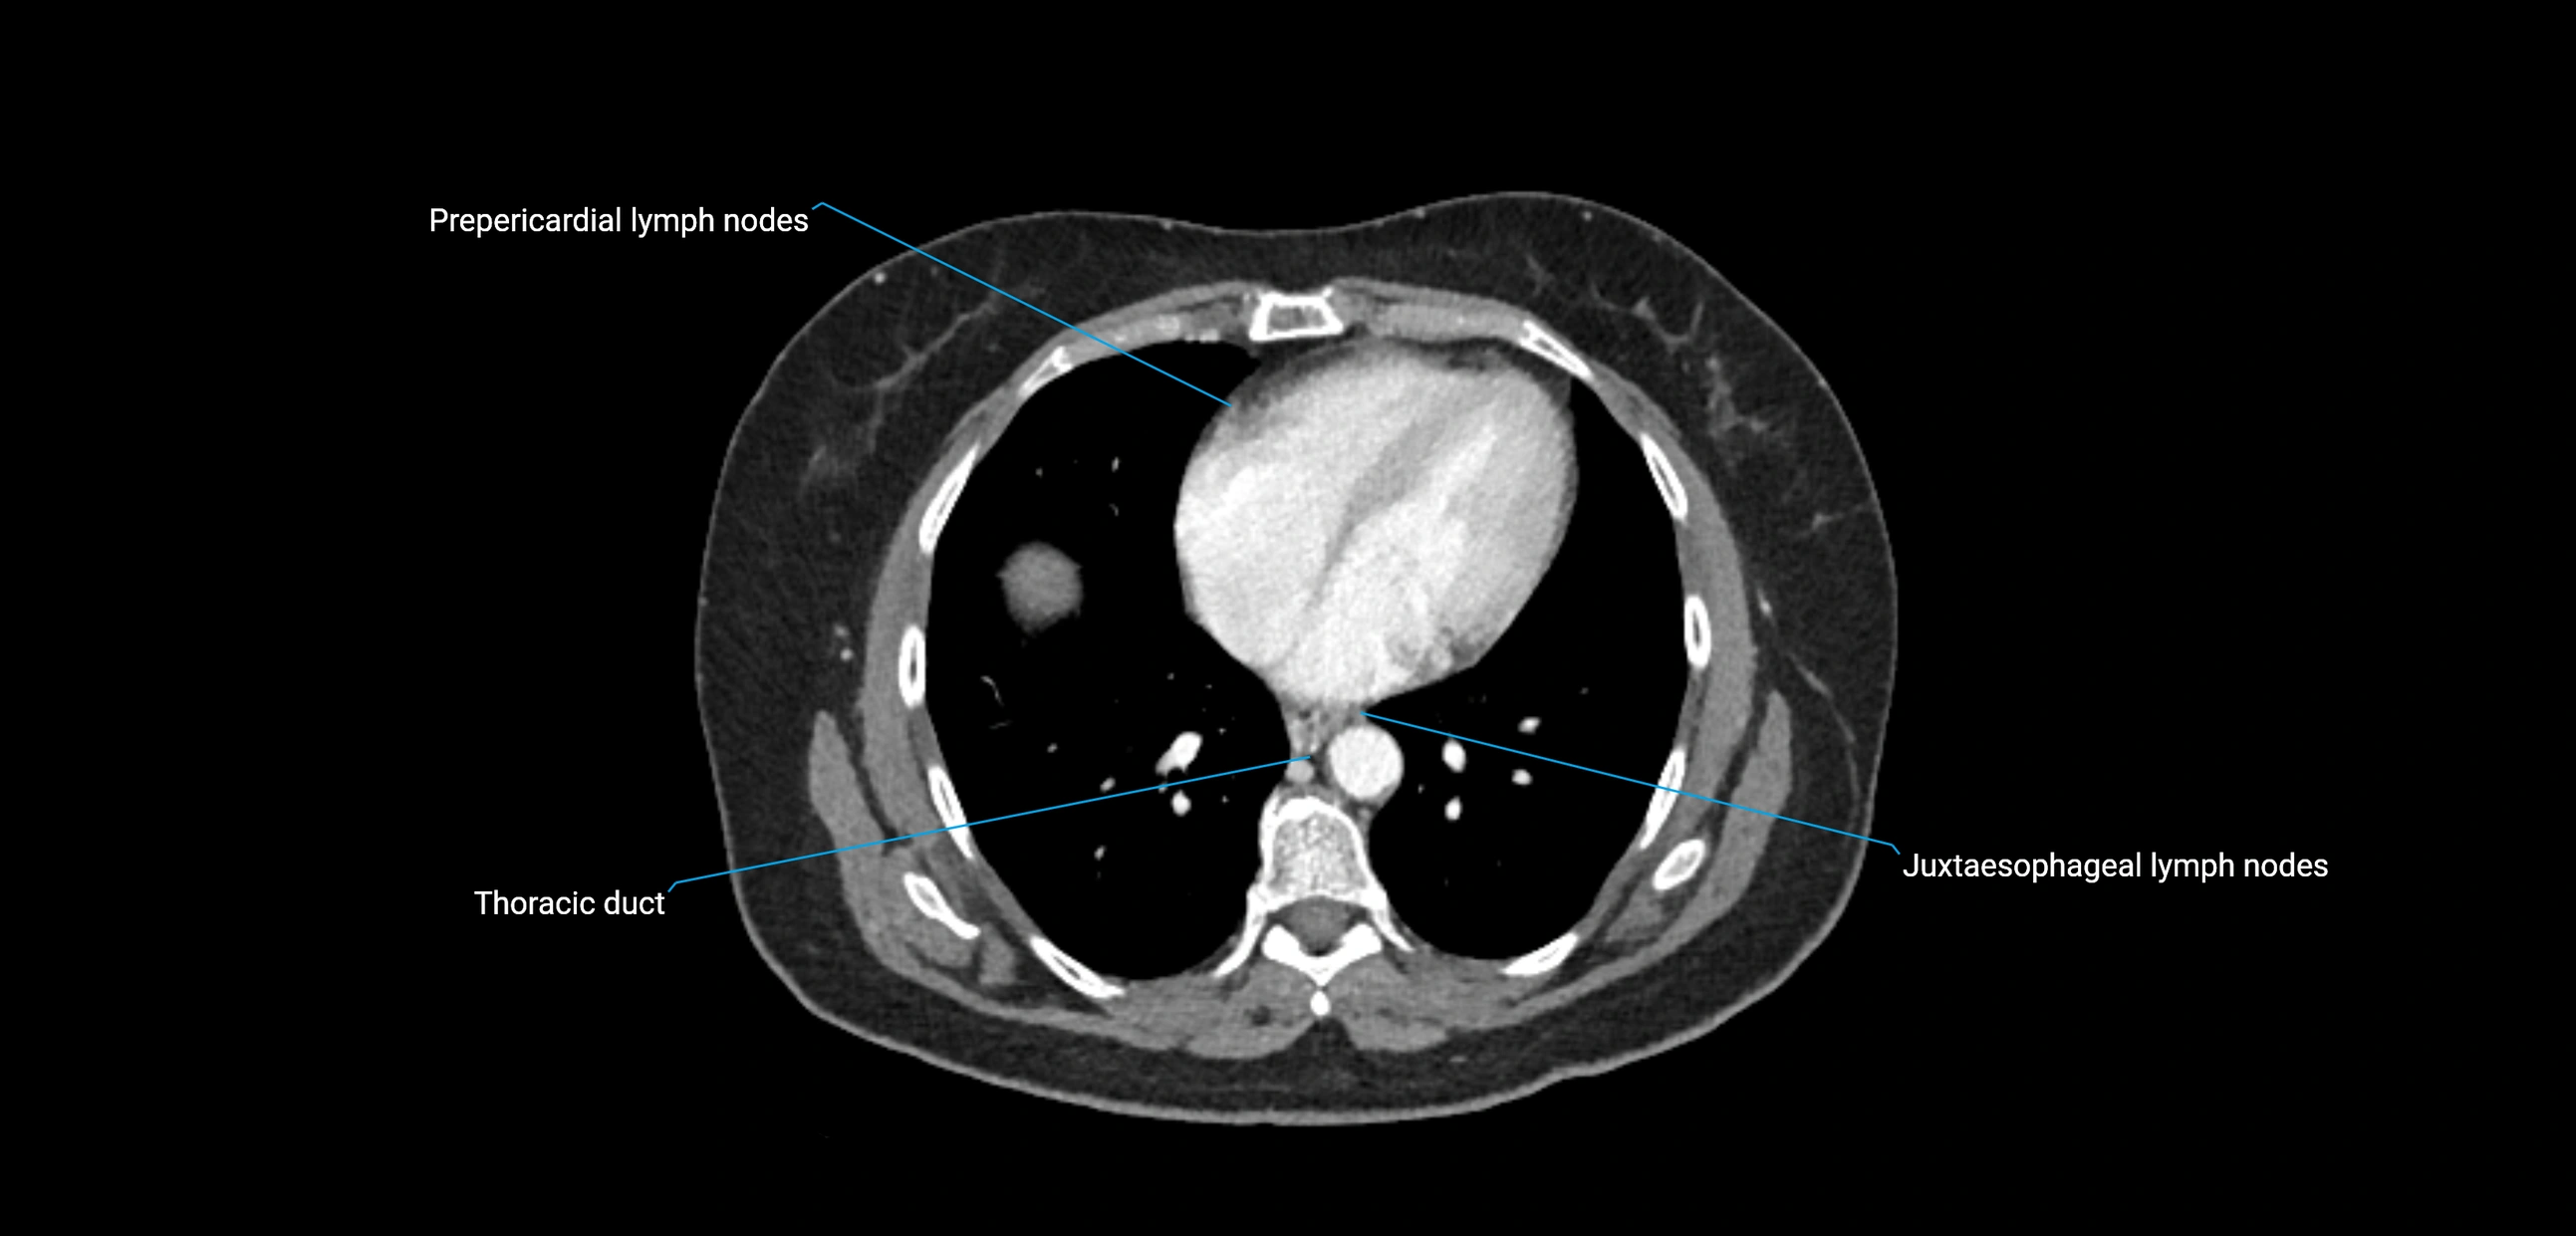

CT image

image